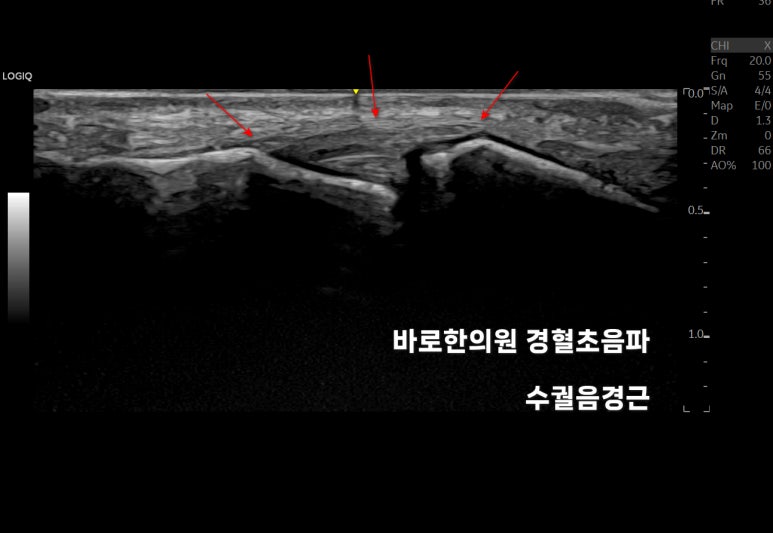

손가락 경혈 초음파

힘줄과 관절을

체크해봅니다.

하나로 연결되어 있어야 할

중지골(middle phalanx)이

끊겨져 보입니다.

동영상으로 보시면사선으로 골절선이 보입니다.